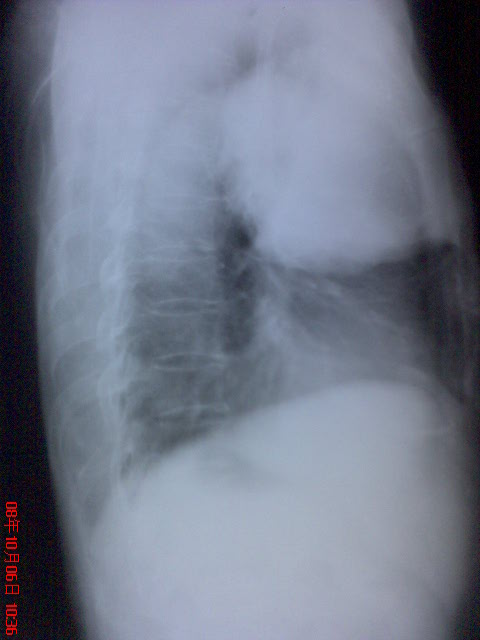

患者作过ct检查,结论是右中上肺占位,考虑直肠癌肺转移?,肺横纹肌肉瘤?,血管平滑肌瘤?建议进一步检查.因家境贫寒,没能做病检。

右中上肺占位,考虑直肠癌肺转移?,肺肉瘤?

只能考虑右上肺巨大占位,至于是结肠癌转移还是肺癌肉瘤没有特征性改变,应结合病理检查。

右上肺占位,考虑1周围型肺癌,2肺肉瘤

考虑右中上肺巨大占位。结肠癌转移还是肺癌肉瘤,结合病理再诊断吧